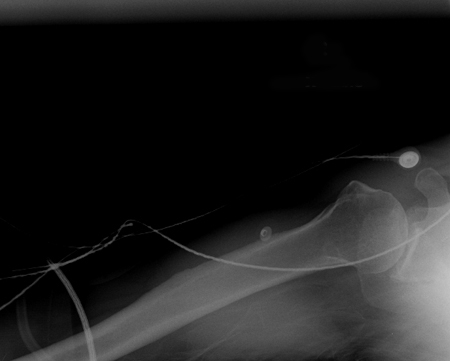

Joint dislocation

Scapular Y x-ray view showing an anterior fracture dislocation of the shoulder and fracture of the greater tuberosity

Personal collection of Dr Paul Novakovich